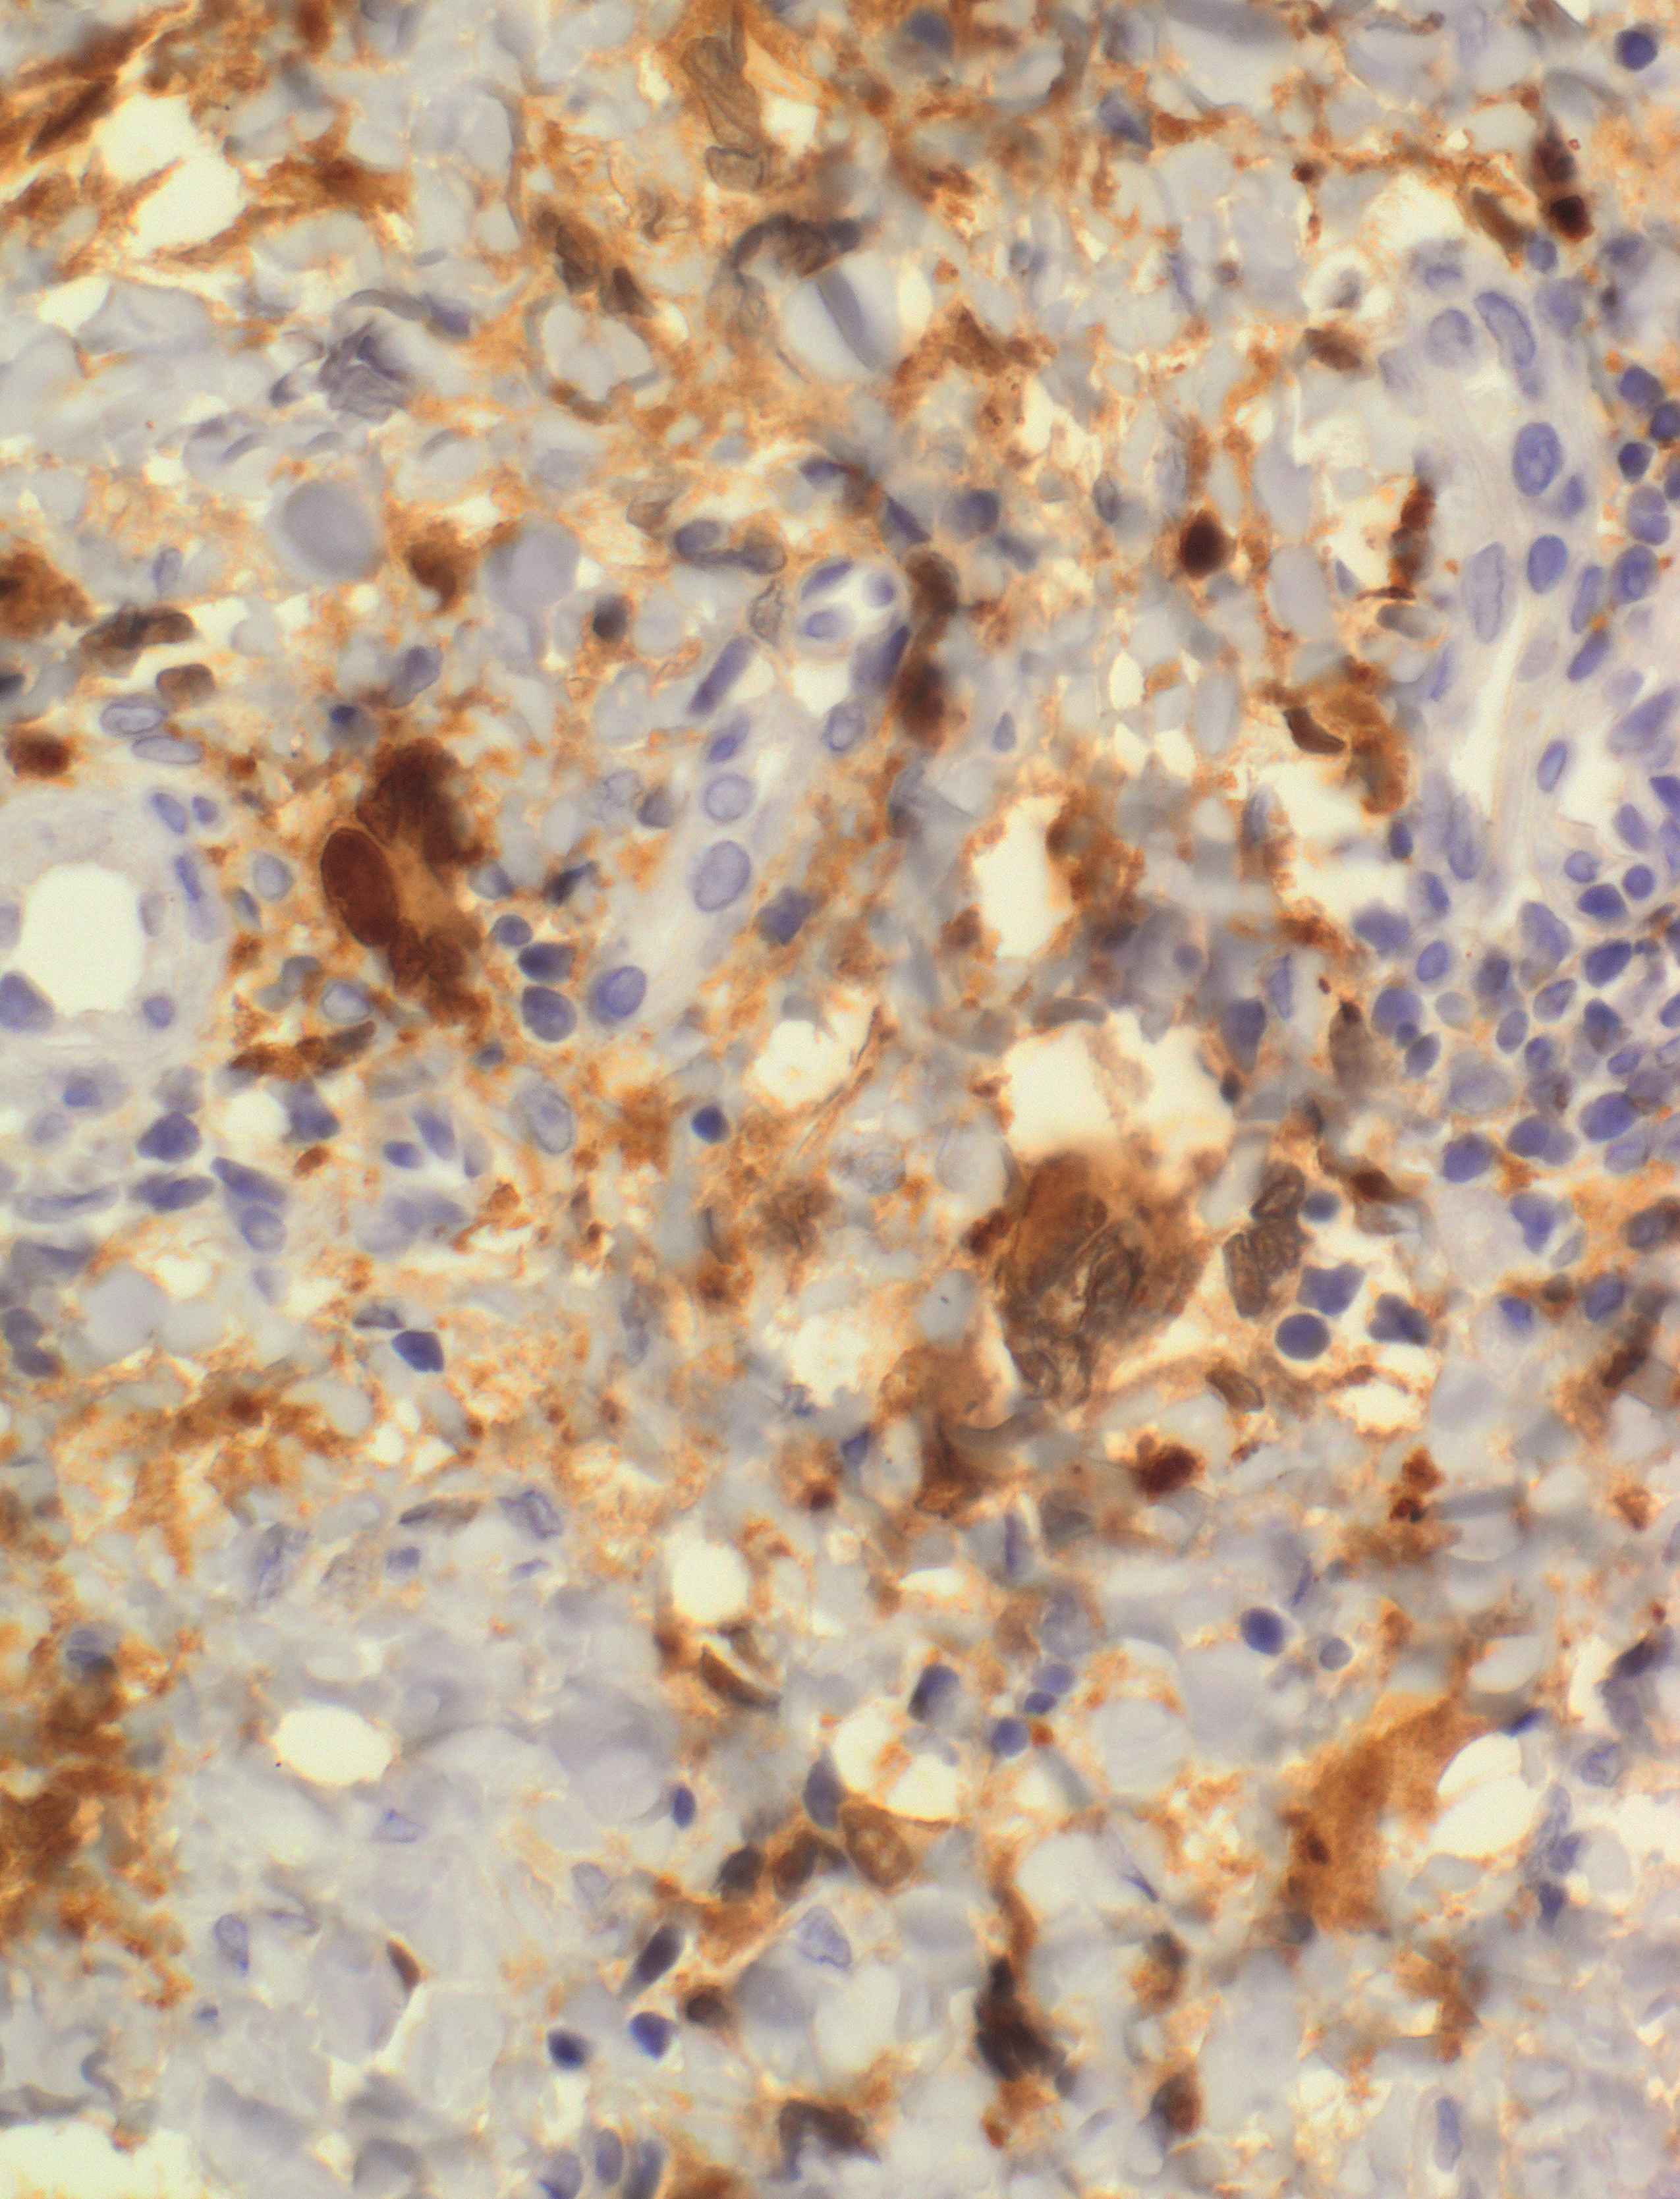

S100 staining of a Rosai-Dorfman disease–like histiocytic lesion with emperipolesis from a patient with H syndrome, a genetic disorder predisposing to histiocytosis. The germ line SLC29A3 mutation induces pathological activation of mitogen-activated protein kinase signaling by a noncanonical pathway. See the article by Shiloh et al on page 1740.